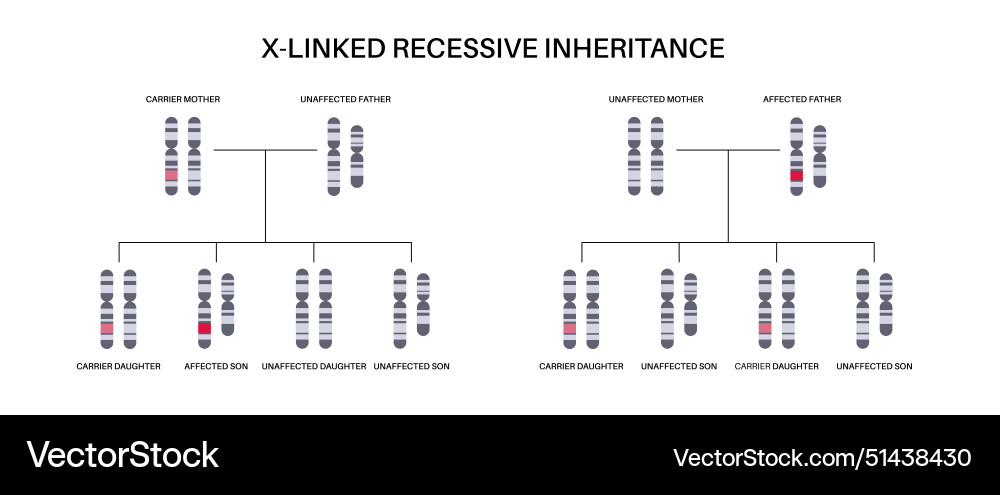

- 51438430

- Chromosome

- Female

- Syndrome

- Fragile

- Inheritance

- Linked

- X

- Carrier

- Disease

- Disorder

- Gene

- Genetic

- Affected

- Child

- Family

- Male

- Offspring

- Parent

- Allele

- Daughter

- Father

- Mother

- Son